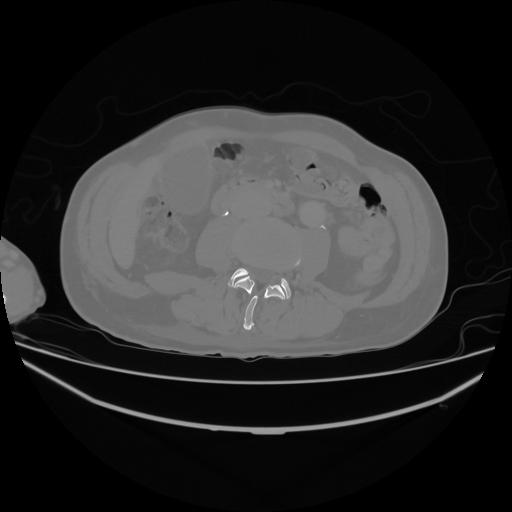

5 CUERPO,CE,Vol,1.0,CUERPO,,